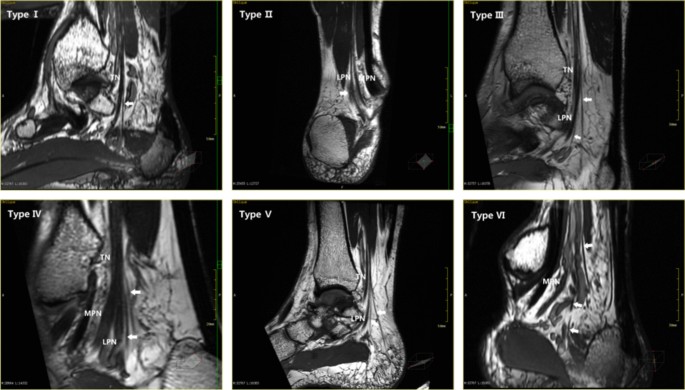

The occurrence rate of the medial calcaneal nerve (MCN) was 100%, although the number and starting position of the nerve varied greatly. Segmental reformation showed that the distal part of the nerve was located behind the calcaneal tuberosity and the subcutaneous tissue of the heel. Out of the 40 images in our study, 18 had a single medial calcaneal nerve, 21 had two medial calcaneal nerves, and only one had three medial calcaneal nerves. From the position of origin, the medial calcaneal nerve started from the tibial nerve, the plantar nerve, the lateral nerve bifurcation point, and the lateral plantar nerve. A medial calcaneal nerve originating from the medial plantar nerve was not found. Based on the MPR data, we divided the medial calcaneal nerve into major types, as shown in Figs. 8 and 9.

Modes of origins of the medial calcaneal nerve: Type I a medial calcaneal nerve originating from the tibial nerve; Type II a medial calcaneal nerve originating from the lateral plantar nerve; Type III two medial calcaneal nerves, one originated from the tibial nerve, and the other originated from lateral plantar nerve; Type IV two medial calcaneal nerves, both originated from tibial nerve; Type V two medial calcaneal nerves, with a common origin on the tibial nerve; Type VI three medial calcaneal nerves, one originated from the tibial nerve and the other two originated from the lateral plantar nerve

The medial calcaneal nerve is one of the main branches of the tibial nerve, terminating in the skin of the heel and the weight-bearing surface, and providing sensory innervation to the inner posterior side of the heel [26, 27]. The starting position and the number of medial calcaneal nerves vary greatly. Quantitatively, Dellon et al. [28] found that 37% had one medial calcaneal nerve, 41% had two medial calcancal nerves, 19% had three medial calcancal nerves, and 3% had four medial calcancal nerves. Kim et al. [29] and Yang et al. [10] found that there were up to five medial calcaneal nerves. Govsa et al. [11] and Kim et al. [29] indicated that there were two common vessels on the medial surface of the calcaneus. In this study, up to three medial calcaneal nerves were reformatted, which may be related to the small number of samples. However, a maximum of two medial calcaneal nerves were reformatted in this study, which is consistent with the above-mentioned views. At the starting point, the medial calcaneal nerve may originate from the tibial nerve, the medial and lateral plantar nerve bifurcation points, and the lateral plantar nerve. Havel et al. [30] and Dellon et al. [28] found that the medial calcaneal nerve can also originate from the medial plantar nerve. These differences are mainly related to more than one calcaneal nerve in most cases, indicating the high rate of variation in the origin of the medial calcaneal nerve. Although the medial calcaneal nerve can originate from the tibial nerve to the lateral plantar nerve, segmental reformation showed that its terminal branches showed a consistent range of innervation, all of which went to the heel skin behind the calcaneal tuberosity, which was consistent with anatomic conclusions [10, 11, 29, 31].